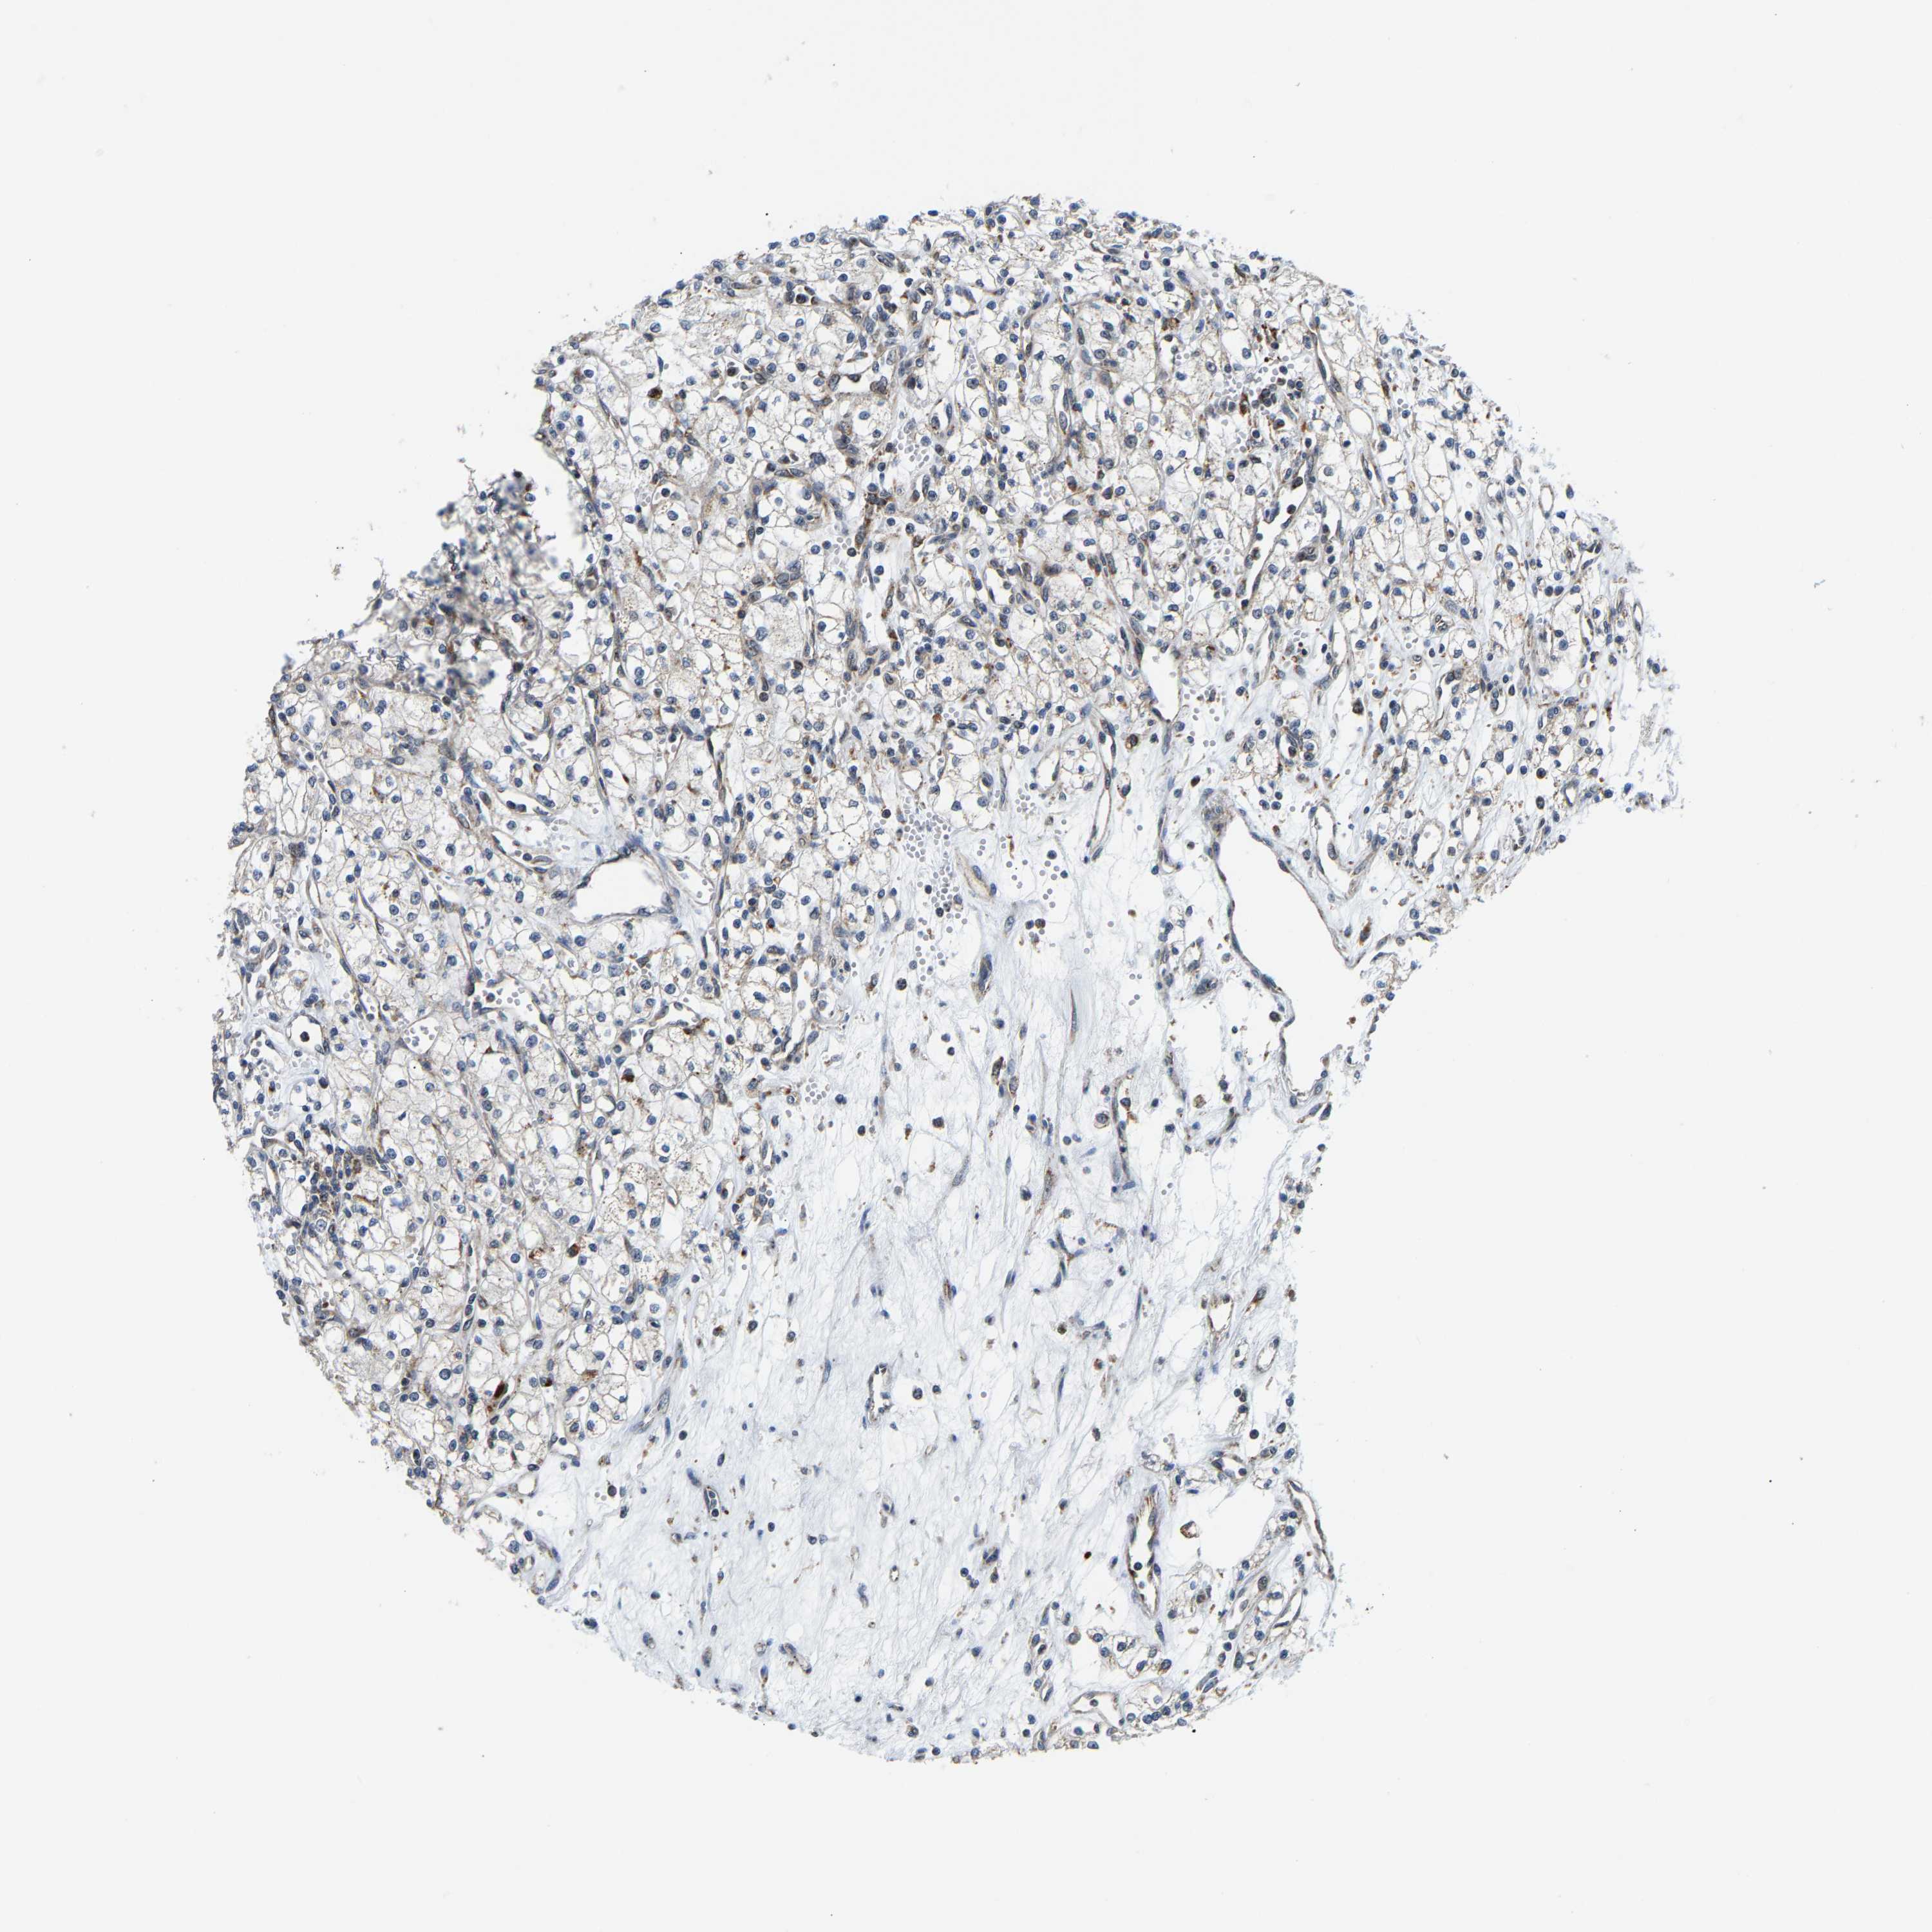

KIDNEY RENAL CLEAR CELL CARCINOMA (VALIDATION) - Interactive survival scatter ploti

The Survival Scatter plot shows the clinical status (i.e. dead or alive) for all individuals in the patient cohort, based on the same data that underlies the corresponding Kaplan-Meier plots. Patients that are alive at last time for follow-up are shown in blue and patients who have died during the study are shown in red.

The x-axis shows the expression levels (FPKM) of the investigated gene in the tumor tissue at the time of diagnosis. The y-axis shows the follow-up time after diagnosis (years). Both axes are complimented with kernel density curves demonstrating the data density over the axes. The top density plot shows the expression levels (FPKM) distribution among dead (red) and alive patients (blue). The right density plot shows the data density of the survived years of dead patients with high and low expression levels respectively, stratified using the cutoff indicated by the vertical dashed line through the Survival Scatter plot. This cutoff is automatically defined based on the FPKM cutoff that minimizes the p-score. The cutoff can be changed by dragging the vertical line or by entering a cutoff value in the square labeled "Current cut-off".

Under the Survival Scatter plot the p-score landscape (black curve; left axis) is shown together with dead median separation (red curve; right axis). Dead median separation is the difference in median mRNA expression between patients who have died with high and low expression, respectively. It is calculated as follows: median FPKM expression of dead patients with high expression - median FPKM expression of dead patients with low expression. This is intended to aid the user in visually exploring custom cutoffs and the associated p-scores and dead median separation.

Individual patient data is displayed and can be filtered by clicking on one or more of the category buttons on the top of the page. Categories describing expression level and patient information include: high, low, alive, dead, female, male and tumor stages. The scale of the x-axis can be toggled between linear and log-scale by clicking on the "x log" button. Mouse-over function shows TCGA ID, patient information and mRNA expression (FPKM) for each patient.

& Survival analysisi

Kaplan-Meier plots summarize results from analysis of correlation between mRNA expression level and patient survival. Patients were divided based on level of expression into one of the two groups "low" (under cut off) or "high" (over cut off). X-axis shows time for survival (years) and y-axis shows the probability of survival, where 1.0 corresponds to 100 percent.

GIMAP7 is not prognostic in Kidney Renal Clear Cell Carcinoma (validation)

Best expression cut offi

Based on the FPKM value of each gene, patients were classified into two groups and association between prognosis (survival) and gene expression (FPKM) was examined. The best expression cut-off refers the FPKM value that yields maximal difference with regard to survival between the two groups at the lowest log-rank P-value. Best expression cut-off was selected based on survival analysis .

When clicking on this number, the vertical dashed line indicating cut-off, the interactive survival plot, and the Kaplan-Meier curve will be adjusted to show results based on the best expression cut-off.

: 86.01

P scorei

Log-rank P value for Kaplan-Meier plot showing results from analysis of correlation between mRNA expression level and patient survival.

N/A

5-year survival highi

5-year survival for patients with higher expression than the expression cutoff.

For melanoma and glioma, 3-year survival is shown.

5-year survival lowi

5-year survival for patients with lower expression than the expression cutoff.

TCGA RNA samplesi

RNA-seq data is reported as average FPKM (number Fragments Per Kilobase of exon per Million reads), generated by the The Cancer Genome Atlas (TCGA) .

Normal distribution across the dataset is visualized with box plots, shown as median and 25th and 75th percentiles. Points are displayed as outliers if they are above or below 1.5 times the interquartile range. FPKM values of the individual samples are presented next to the box plot.

Average pTPM 66.8

Number of samples 100